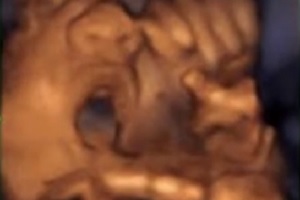

Dispositivo promete estimular movimentos de vocalização no feto (boca e língua) a partir da 16ª semana

Em estudo publicado em 2015 na revista científica “Ultrasound”, da Sociedade Médica Britânica de Ultrassom, pesquisadores da Faculdade de Medicina da Universidade de Barcelona, na Espanha, e do Instituto Marquês, também de Barcelona, relataram as reações de fetos ao estímulo musical intravaginal, com o objetivo de identificar as reações a estes estímulos e o período ideal para inicia-los. Segundo os pesquisadores, os resultados do seguimento de 106 gestações sugerem que as vias neurais que participam do sistema auditivo-motor são desenvolvidas logo a partir da 16ª semana gestacional. Também foram listados os vários tipos de reações registradas em exames de imagem por ultrassom 3D e 4D Segundo os pesquisadores, essas descobertas poderiam contribuir para métodos de diagnóstico para triagem auditiva pré-natal e pesquisas sobre estimulação neurológica fetal.

Assista ao vídeo das reações dos fetos ao estímulo musical: